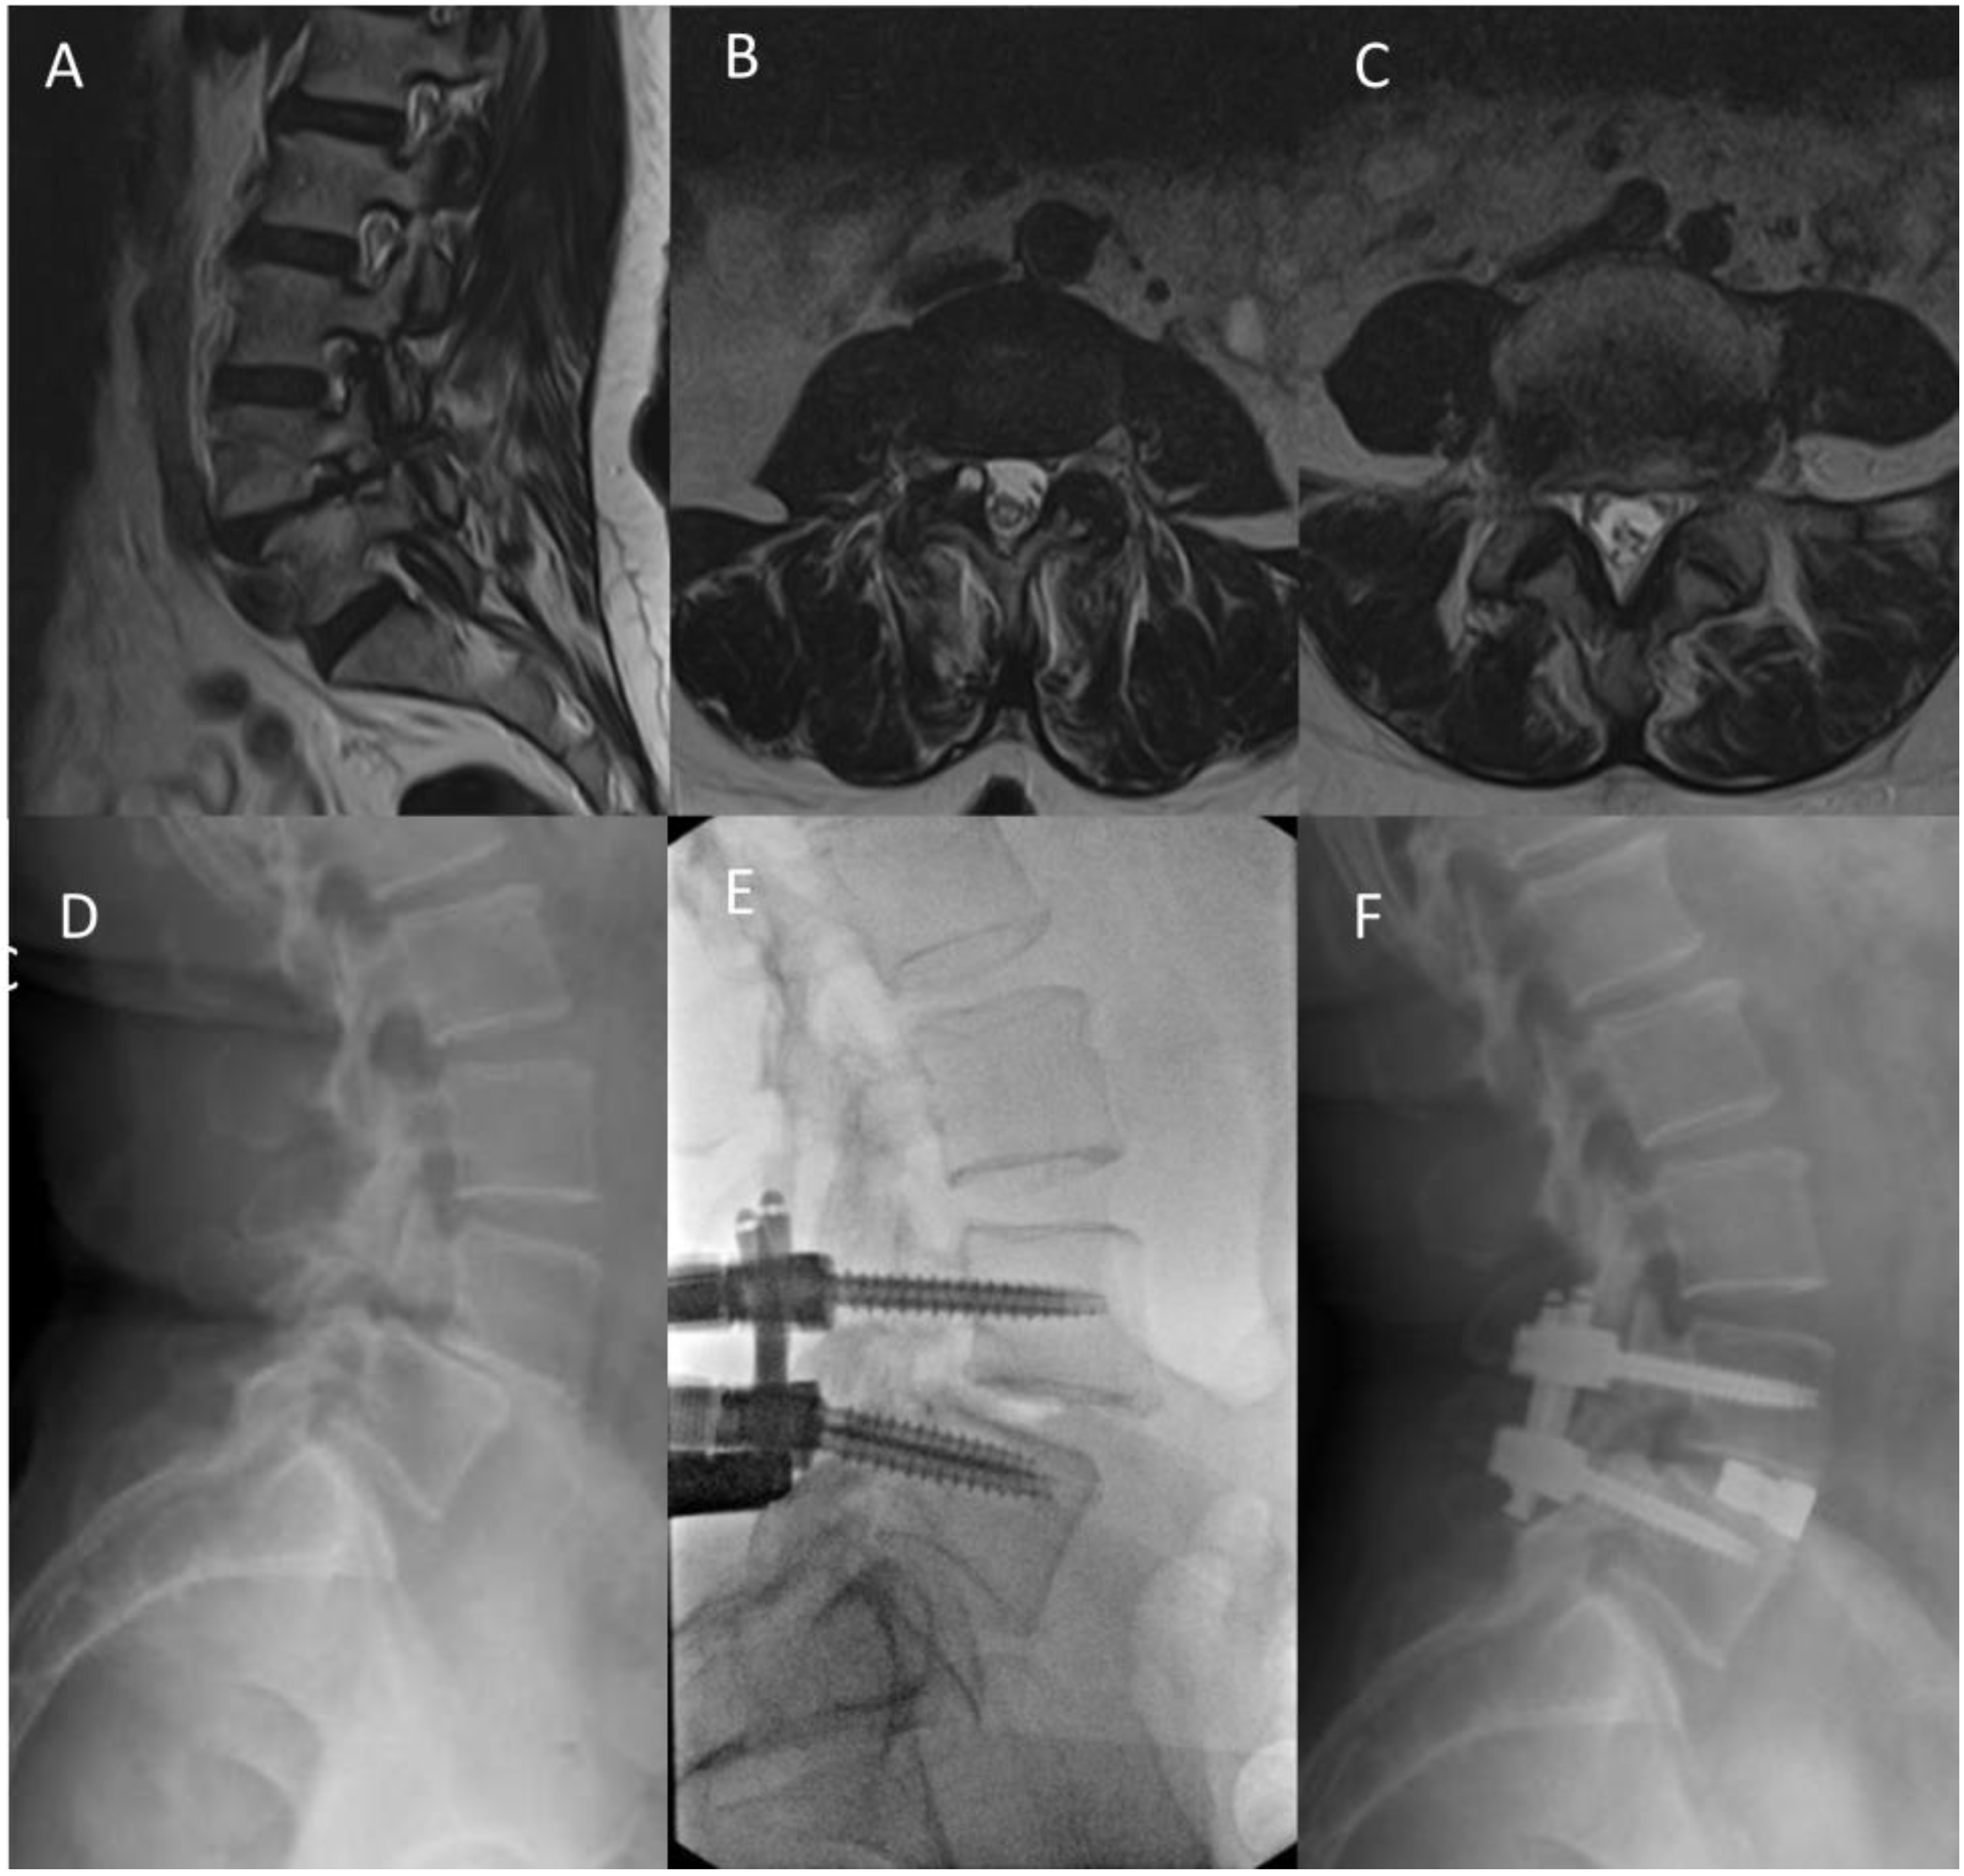

4.1. Case 1